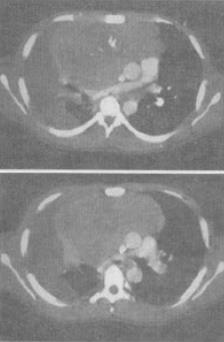

- 单项选择题 患者女,34岁,咳嗽,咯血半个月余,结合影像学检查,最可能的诊断是()。

- A